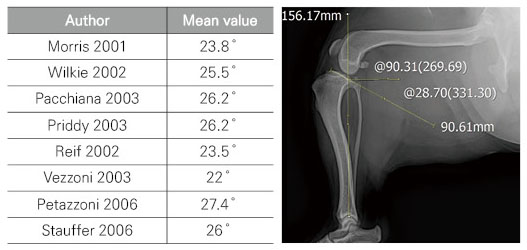

■ TPA란?

• Tibial Plateau Angle

• TPA mean values

■ Preoperative TPA chart